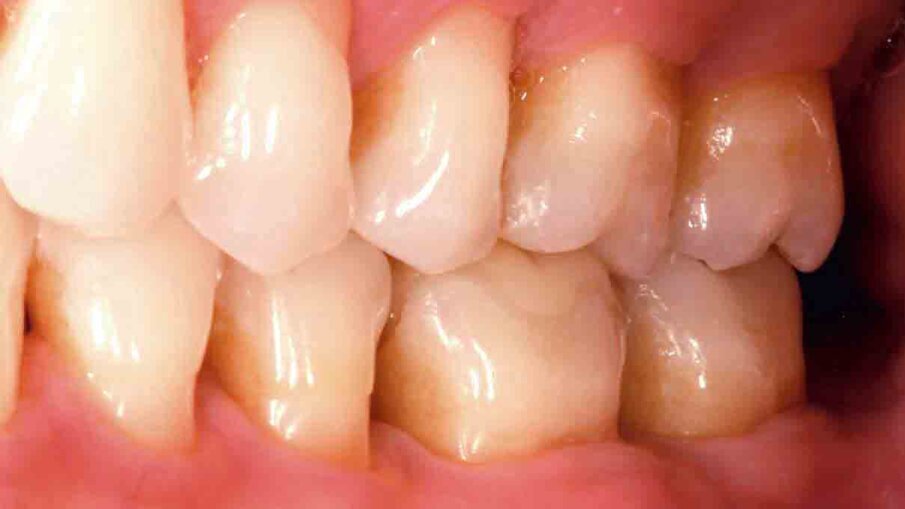

Fig. 10: Situation after crown placement, removal of the excess cement and thorough cleaning. The crown blends in nicely with the surrounding tooth structure.

Fig. 11: At the check-up several days after crown placement, a great overall picture is obtained. The patient is happy with the final restoration in terms of aesthetics and function.